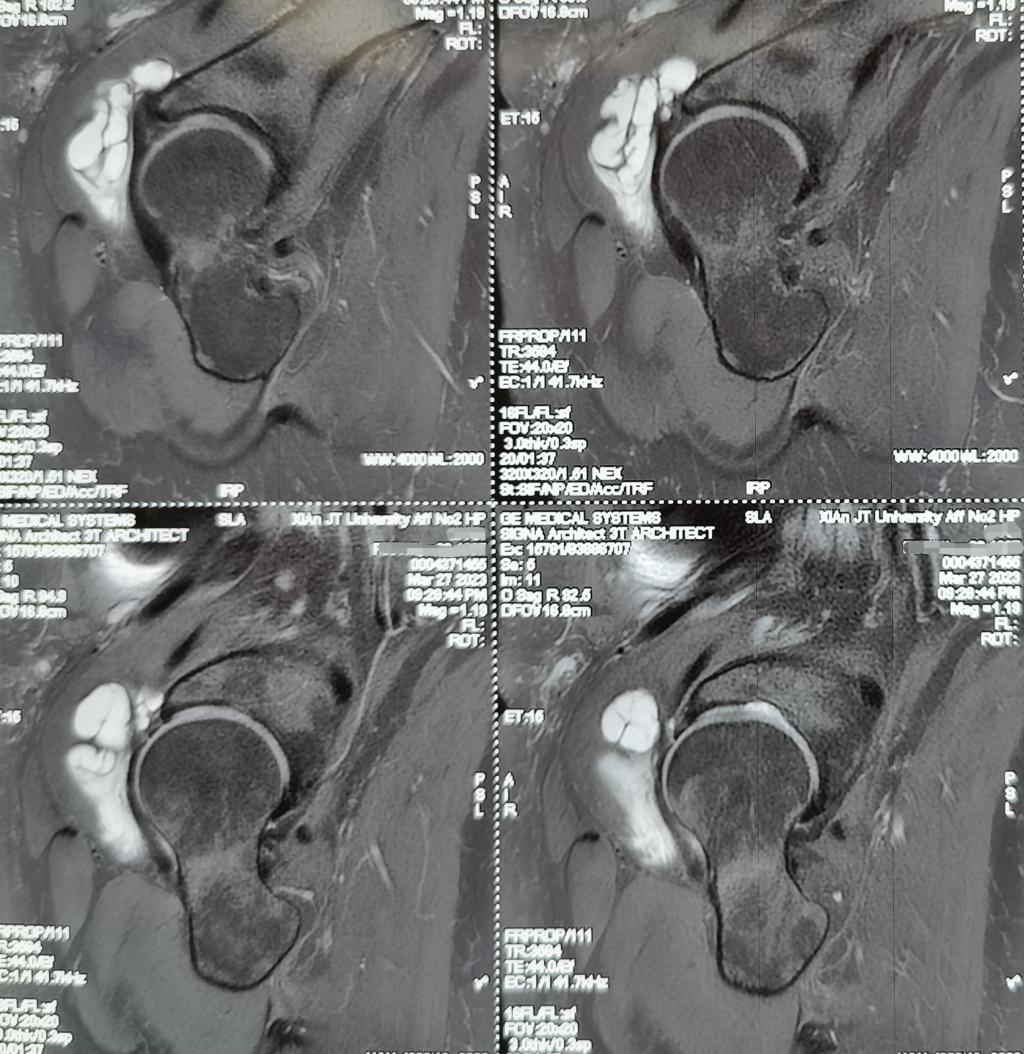

术前核磁